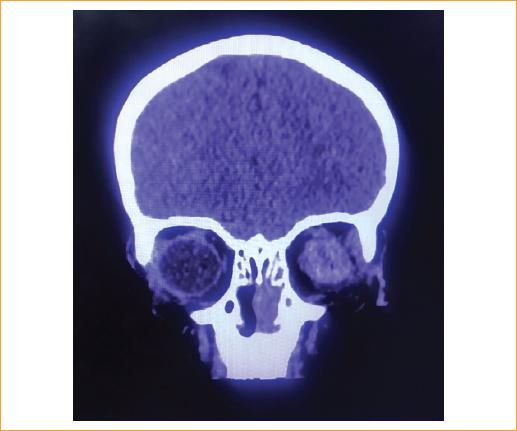

El paciente presentó baja visual, sangrado y dolor (Figs. 1 y 2). A la exploración física presentó agudeza visual del ojo izquierdo en no percepción de luz. En los anexos presentó laceración superficial en el canto interno de aproximadamente 5 cm, blefaroedema 2+ y restos de tejido hemático en las pestañas y fondo de saco. En el segmento anterior en el ojo izquierdo presentó estallamiento y colapso del globo ocular izquierdo. Paciente valorado por oftalmología donde se decide manejo quirúrgico con evisceración del ojo izquierdo.